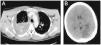

Inmediatamente se coloca drenaje torácico, se obtienen 1.500cm3 de sangre que presenta anemización progresiva a pesar de la transfusión de 4 concentrados de hematíes. La TC de tórax (fig. 2A) evidencia abundantes coágulos y sangre fresca sin hemorragia activa asociada a fracturas costales del 10.0 y 11.0 arco costal.

Después de varias toracocentesis sin obtener sangre y progresiva anemización (Hto 26%, Hb: 8 g/l, plaquetas 643.000/mm3), se realiza toracotomía posterior amiotómica y se evacuan abundantes coágulos observándose las fracturas costales desplazadas con hemorragia difusa a esa altura, sin lesiones pulmonares, diafragmáticas ni mediastínicas asociadas. Se procede a la evacuación de coágulos, costotomía de los extremos costales fracturados y hemostasia, se consigue la reexpansión pulmonar tras la colocación de 2 drenajes torácicos. A los 2 días presenta hemianopsia derecha con disartria por lo que se realizó TC craneal (fig. 2B) que demuestra infarto establecido de la arteria cerebral posterior izquierda. La ecografía de los troncos supraaórticos y la ecocardiografía son normales y se inicia tratamiento con 300mg de ácido acetilsalicílico.